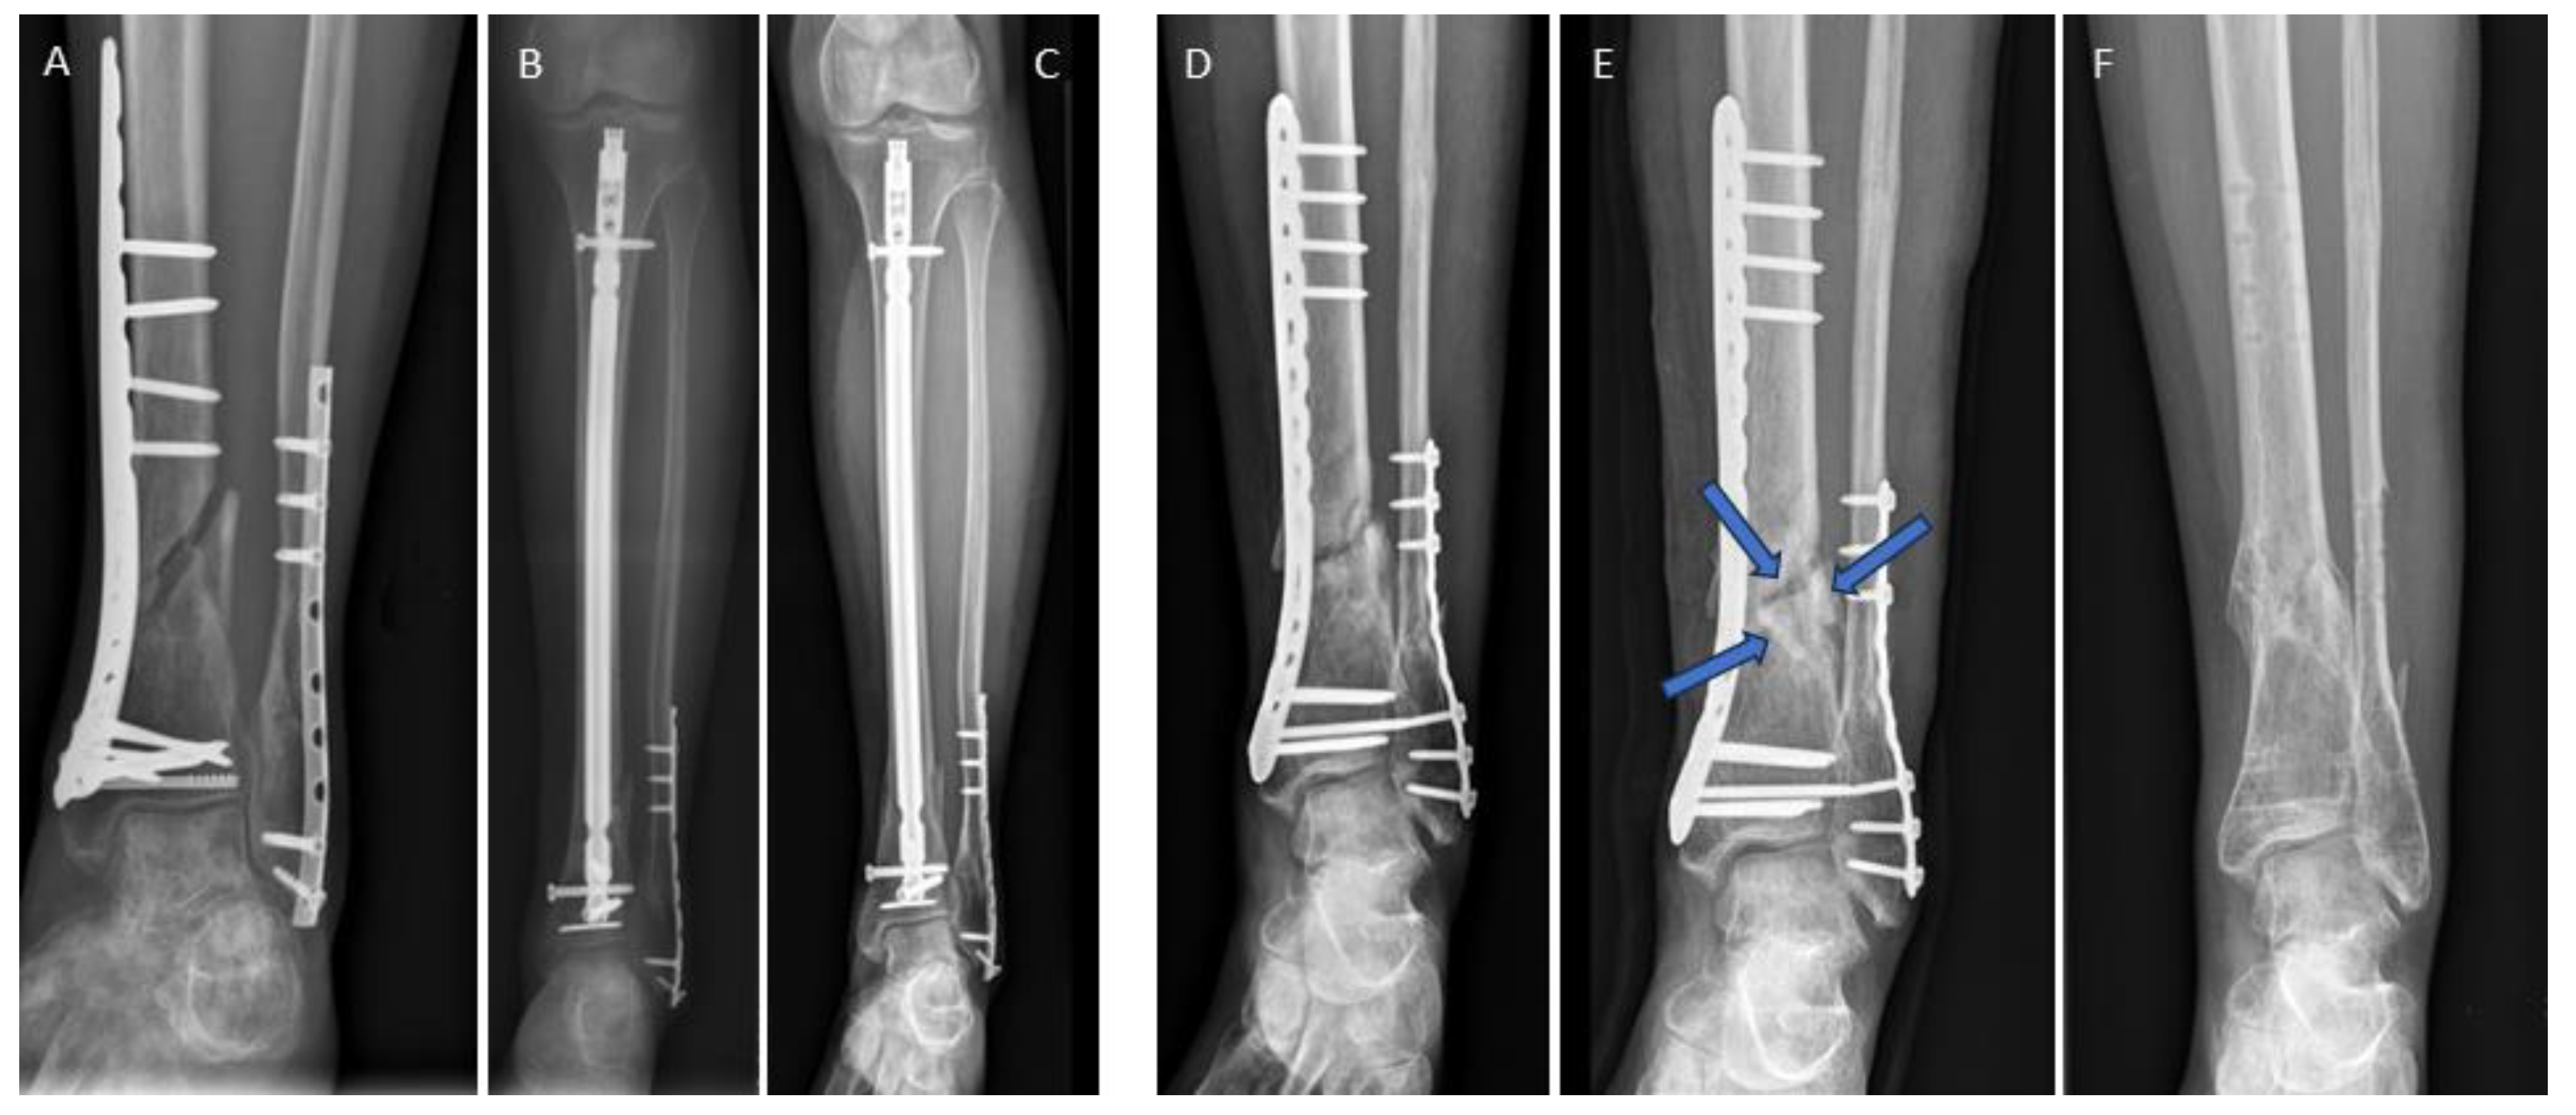

3.4. Examples for Bone Healing

3.6. Radiological Findings of Interest